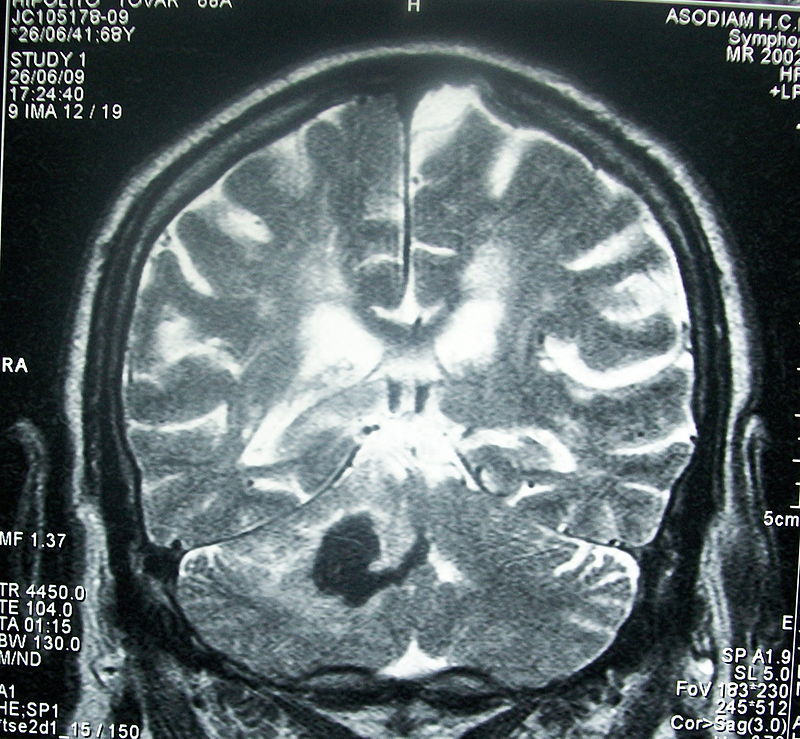

El daño cerebral adquirido hace referencia a cualquier tipo de lesión no degenerativa que se produce en el cerebro, como ictus, traumatismos craneoencefálicos, tumores, etcétera. Este tipo de lesión puede causar un deterioro neurológico permanente que repercute en la calidad de vida del individuo y disminuye su capacidad para realizar tareas de la vida diaria.

En nuestro país, el número de casos de daño cerebral adquirido ha aumentado considerablemente en los últimos años. Los déficits que produce esta enfermedad son muy variados y se pueden englobar en cuatro áreas: cognitivos, emocionales y de conducta, sensoriales y físicos. La persona con estas lesiones pasa por tres fases en su recuperación: aguda, subaguda y crónica. En todas ellas, los tratamientos que se aplican tienden fundamentalmente a que el paciente mantenga las capacidades conservadas. A esos tratamientos tradicionales los investigadores han sumado nuevas técnicas grupales de rehabilitación física que tienden a mejorar la capacidad funcional, la integración en la comunidad y por consiguiente una mayor calidad de vida.